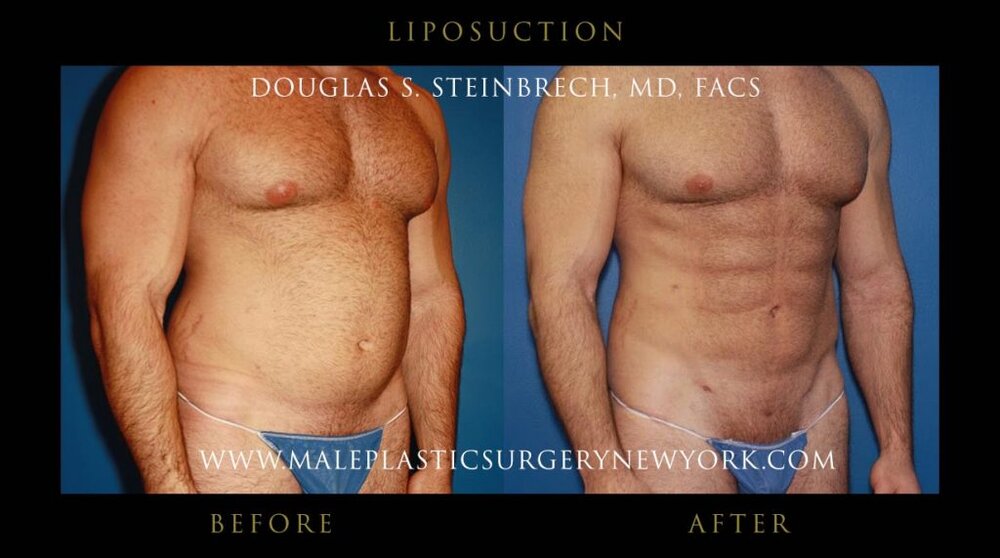

15. Liposuction

15. Liposuction